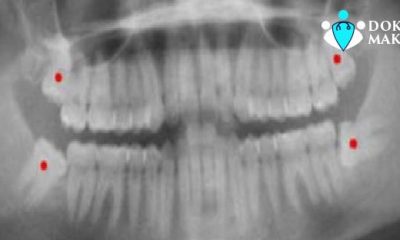

Gömük Diş Nedir? Gömülü 20 'lik dişler: Gömülü diş ve 20 yaş diş Hastalalarının en çok yakındığı şikayetlerinin başında ağrı ve şişlik gelir ...

Gömülü 20 yaş dişlerininin en kıymetli belirtileri ağrı ve şişliktir. Bu bahiste yapılmış yüzlerce makale göstermiştir ki hastanın yaşı ...